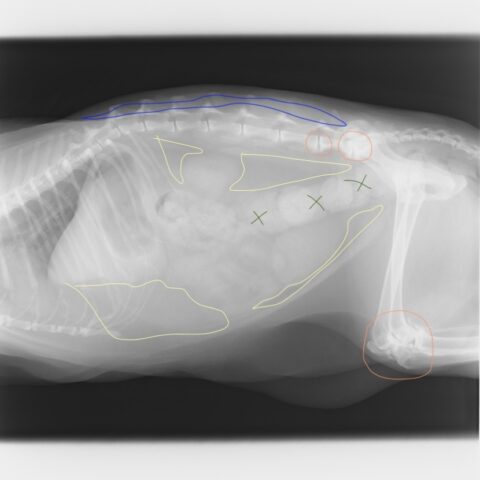

レントゲンの所見

黄色い線の囲み :脂肪・・・内蔵脂肪が多い 肋骨脇から腹部の皮下脂肪が多く胸郭を圧迫している

オレンジの線の囲み :腰椎の変形性脊椎症と膝関節の変形性関節症

緑の✗印 :便秘の便

青線の囲み :MCSの指標である脊椎脇の筋肉の減少